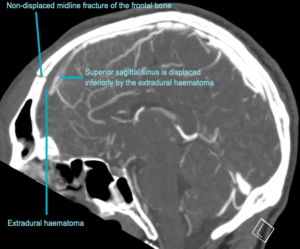

CASE 2 -A 54-year-old man walks into emergency 3 hours after a 150kg plank of wood fell on his head. He has obvious external signs of head injury and a cracking headache, however, neurologically he is intact. A CT head scan is performed

EXPLANATION –There is a depressed right parietal bone fracture with underlying pneumocephalus (indicates an open skull fracture) and a small subdural hematoma.

- Overlying this there is a scalp hematoma.

- There is also a non-displaced fracture in the frontal bone. This fracture crosses the midline and probably has injured the anterior aspect of the superior sagittal sinus.

- Tears of the dural venous sinuses may cause an extradural hematoma (EDH), as in this case. The hematoma is seen external to the compressed superior sagittal sinus.

Extradural bleeds (EDH) are located between the outer layer of dura and endosteal layer of skull. Like in this case, they are usually associated with calvarial fractures.

- They typically demonstrate biconvex or lentiform shape and are limited by sutures as periosteum is attached at the sutures limiting spread of the bleed.

- The source of bleed is arterial in origin, from a middle meningeal artery as opposed to venous in subdural bleeds.

- Up to 10% of EDH are due to venous bleeding, follow the laceration of a dural venous sinus, as we see in this case.

- There is often displacement of the sinus away from the underlying bone. There are three locations characteristic of venous EDH; the vertex, anterior middle cranial fossa and the occipital posterior fossa.

- Hypodense areas within a bleed likely represent unclotted blood suggesting active bleeding.

- As these bleeds are venous, there is not the same urgency for decompression in theatre. In fact, this patient was managed conservatively as operative intervention poses a risk of further damage to the venous sinuses.